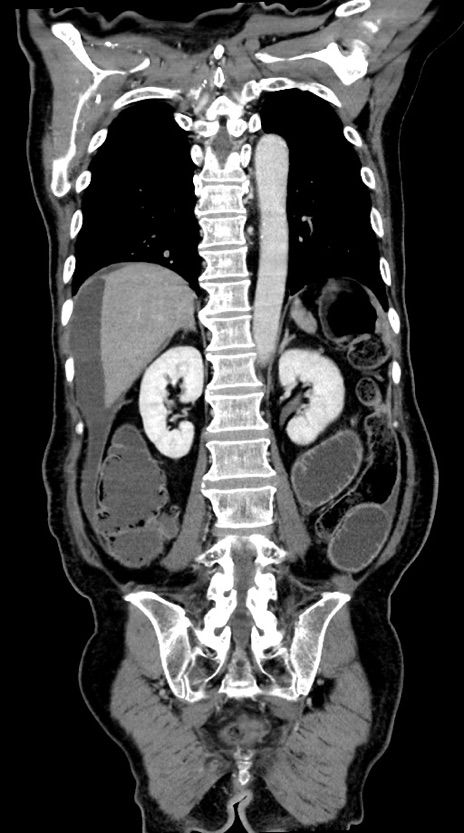

症例28(冠状断像)

【症例】60歳代男性

【主訴】嘔吐

【現病歴】胃癌にて胃全摘後。食思不振が悪化し、夜中に嘔吐することがある。

【既往歴】胃癌、胃全摘、脾摘、胆摘後

【データ】WBC 5900、CRP 10.56